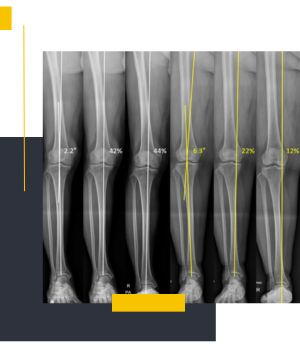

استفاده از دستگاههای دیجیتال نسل جدیدکیفیت بالای تصاویر و نمایش دقیق محور پا باعث میشود تشخیص و ارزیابی پزشکان با اطمینان بیشتری انجام شود.

تهیه عکس در حالت ایستاده برای بررسی واقعی محور اندام

عکسهای الایمنت ویو در مروارید ری طبق استانداردهای ارتوپدی و در وضعیت صحیح ایستاده گرفته میشود تا نتیجه کاملاً دقیق و قابل اعتماد باشد.

تیم مجرب مرکز با انجام روزانه تعداد زیادی از تصاویر اندام تحتانی مهارت بالایی در ثبت درست زاویهها و محورهای استخوانی دارد.